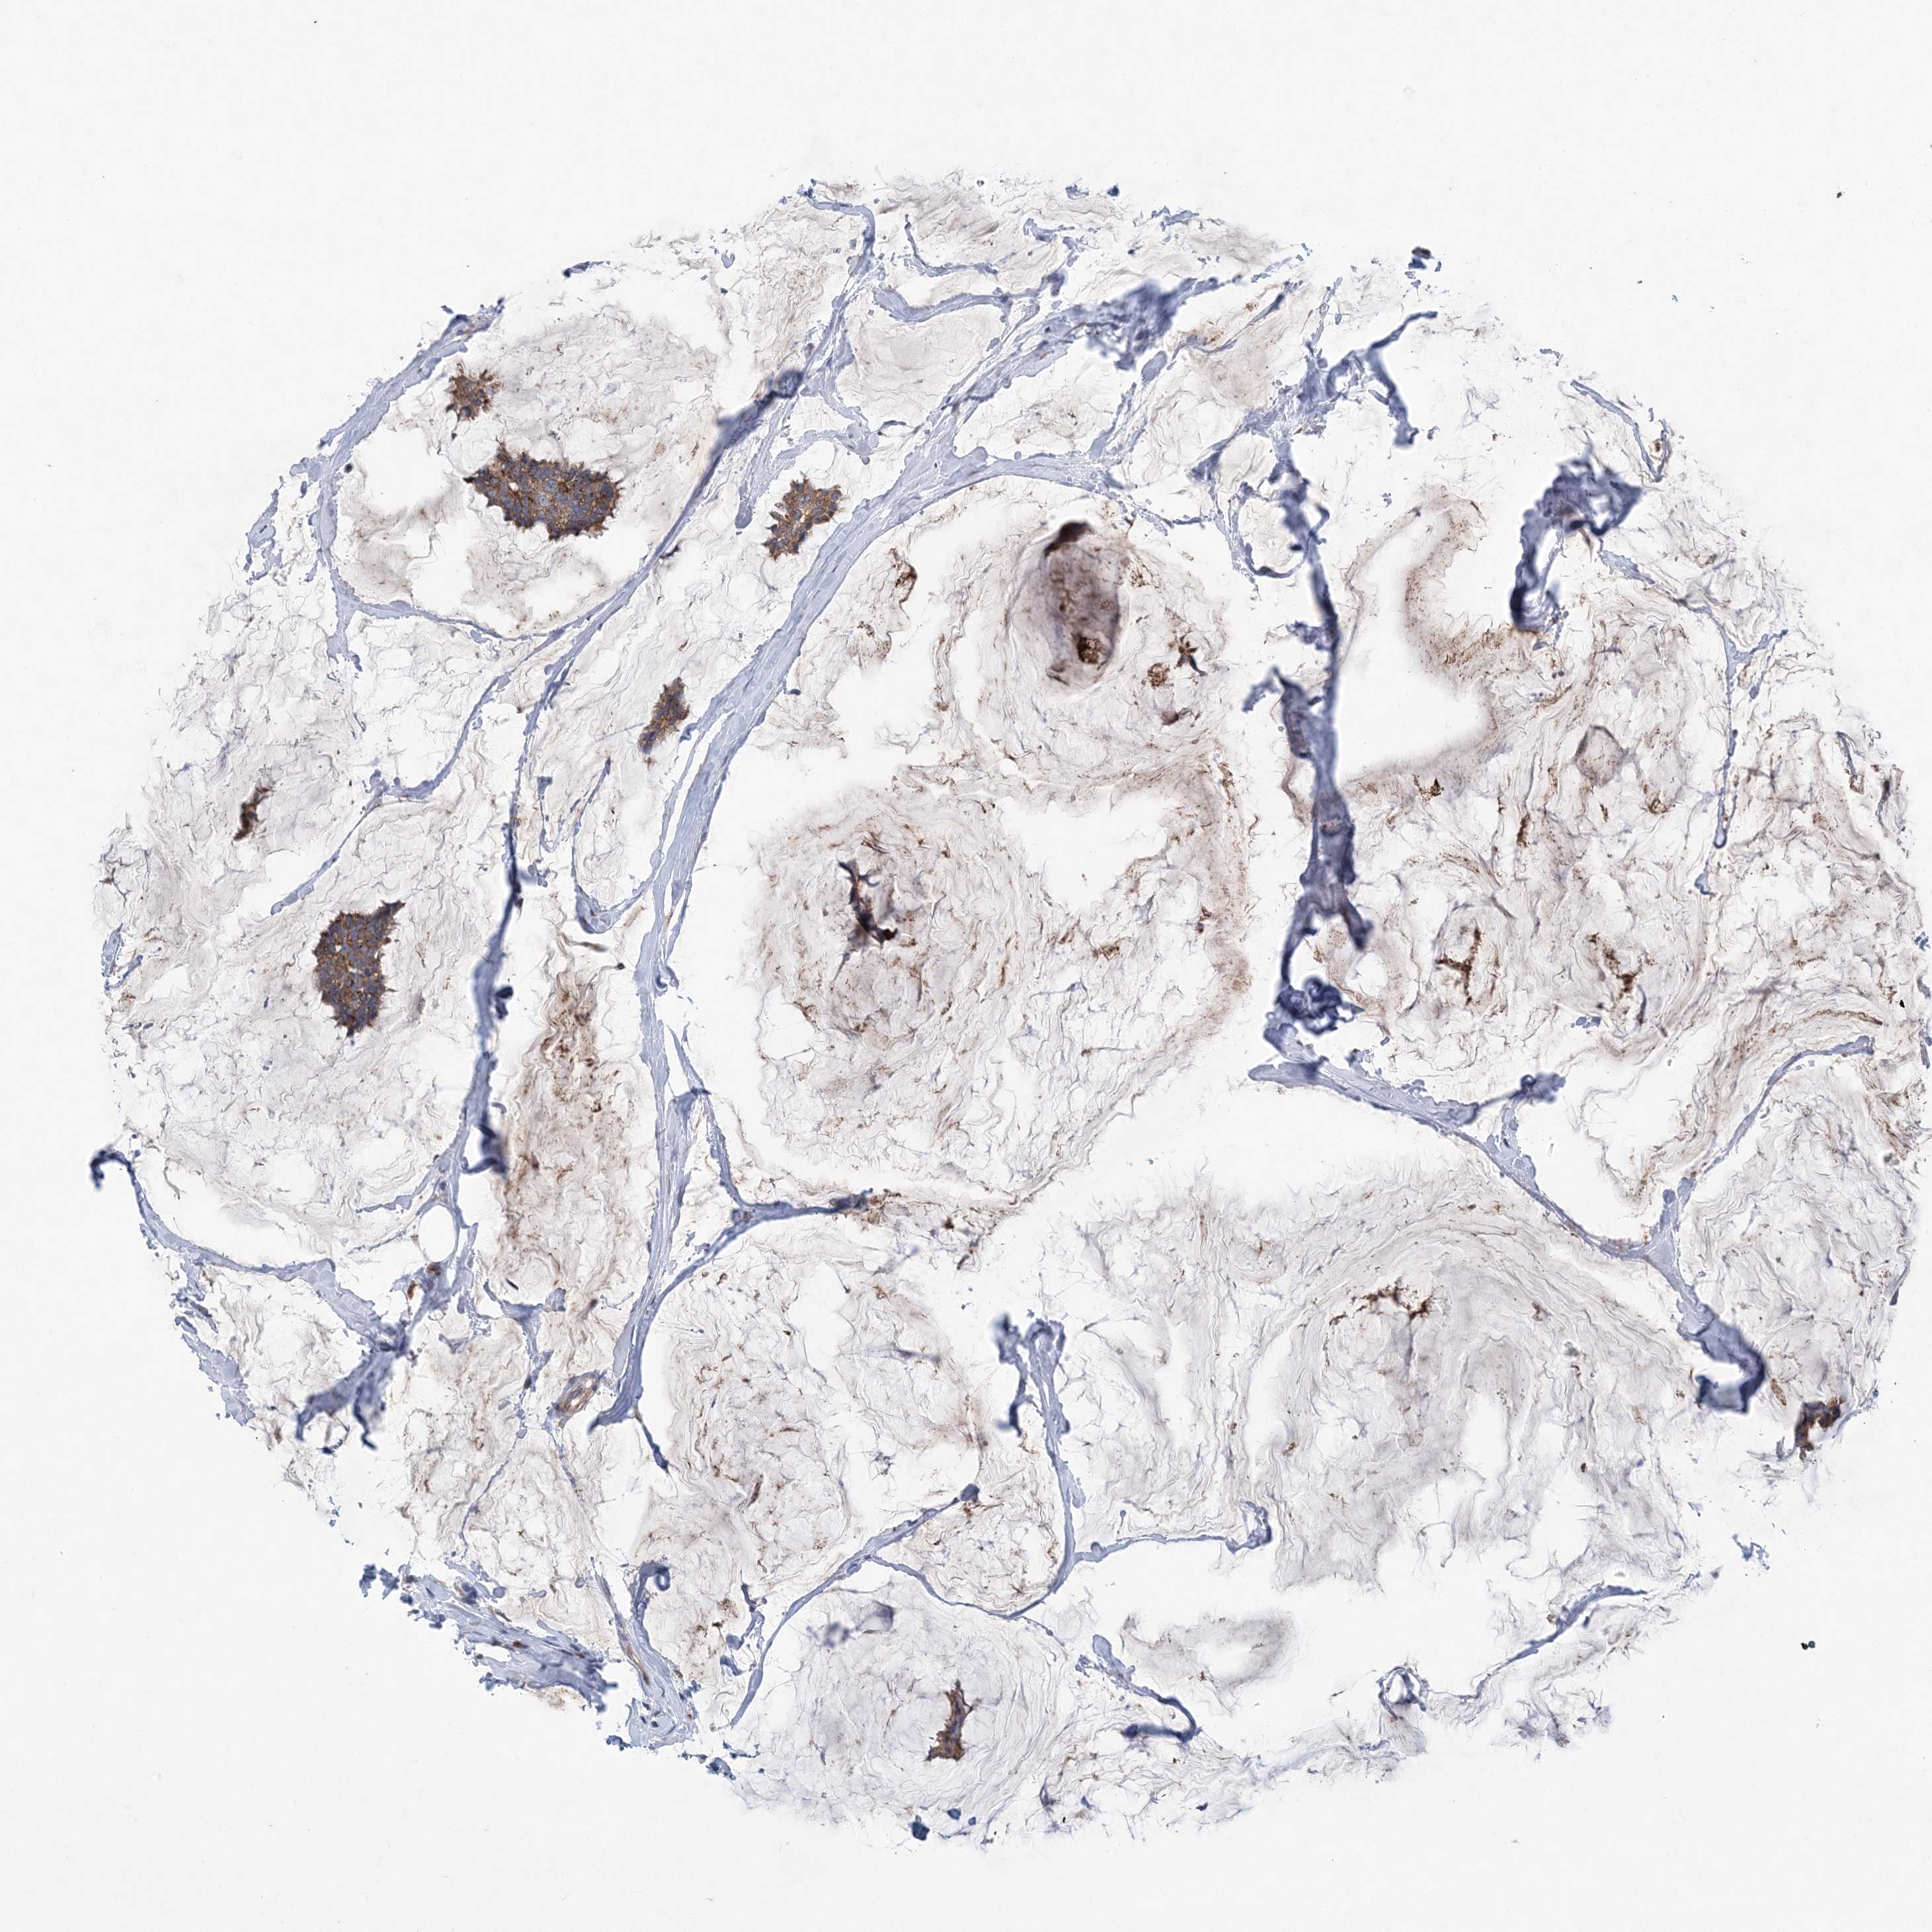

BRCA TCGA BRCA VALIDATION PROTEIN EXPRESSION